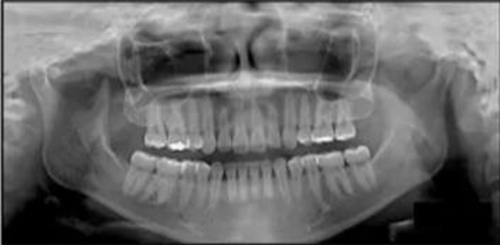

治療后全景片提示間隙得到關(guān)閉,除了左下頜第一前磨牙外牙根平行度可,無(wú)明顯骨及牙根吸收。(圖7)